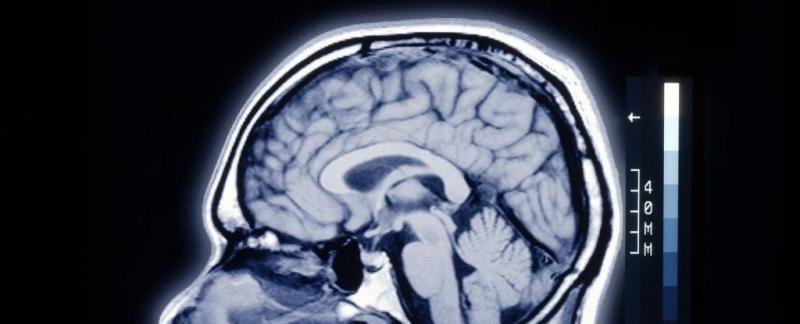

Существует странное различие между мозгом человека и мозгом других млекопитающих